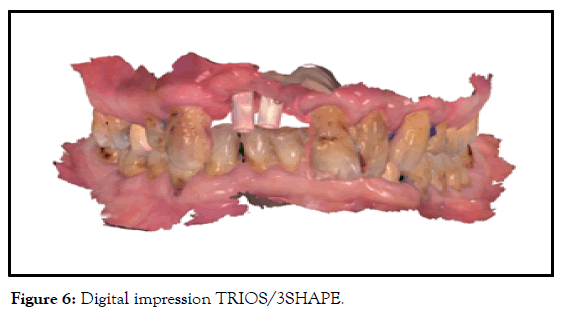

Final reconstruction installed in August 2019 was, splinted/screwed/ zirconium crowns, with Ti bases (Figures 6 and 7).